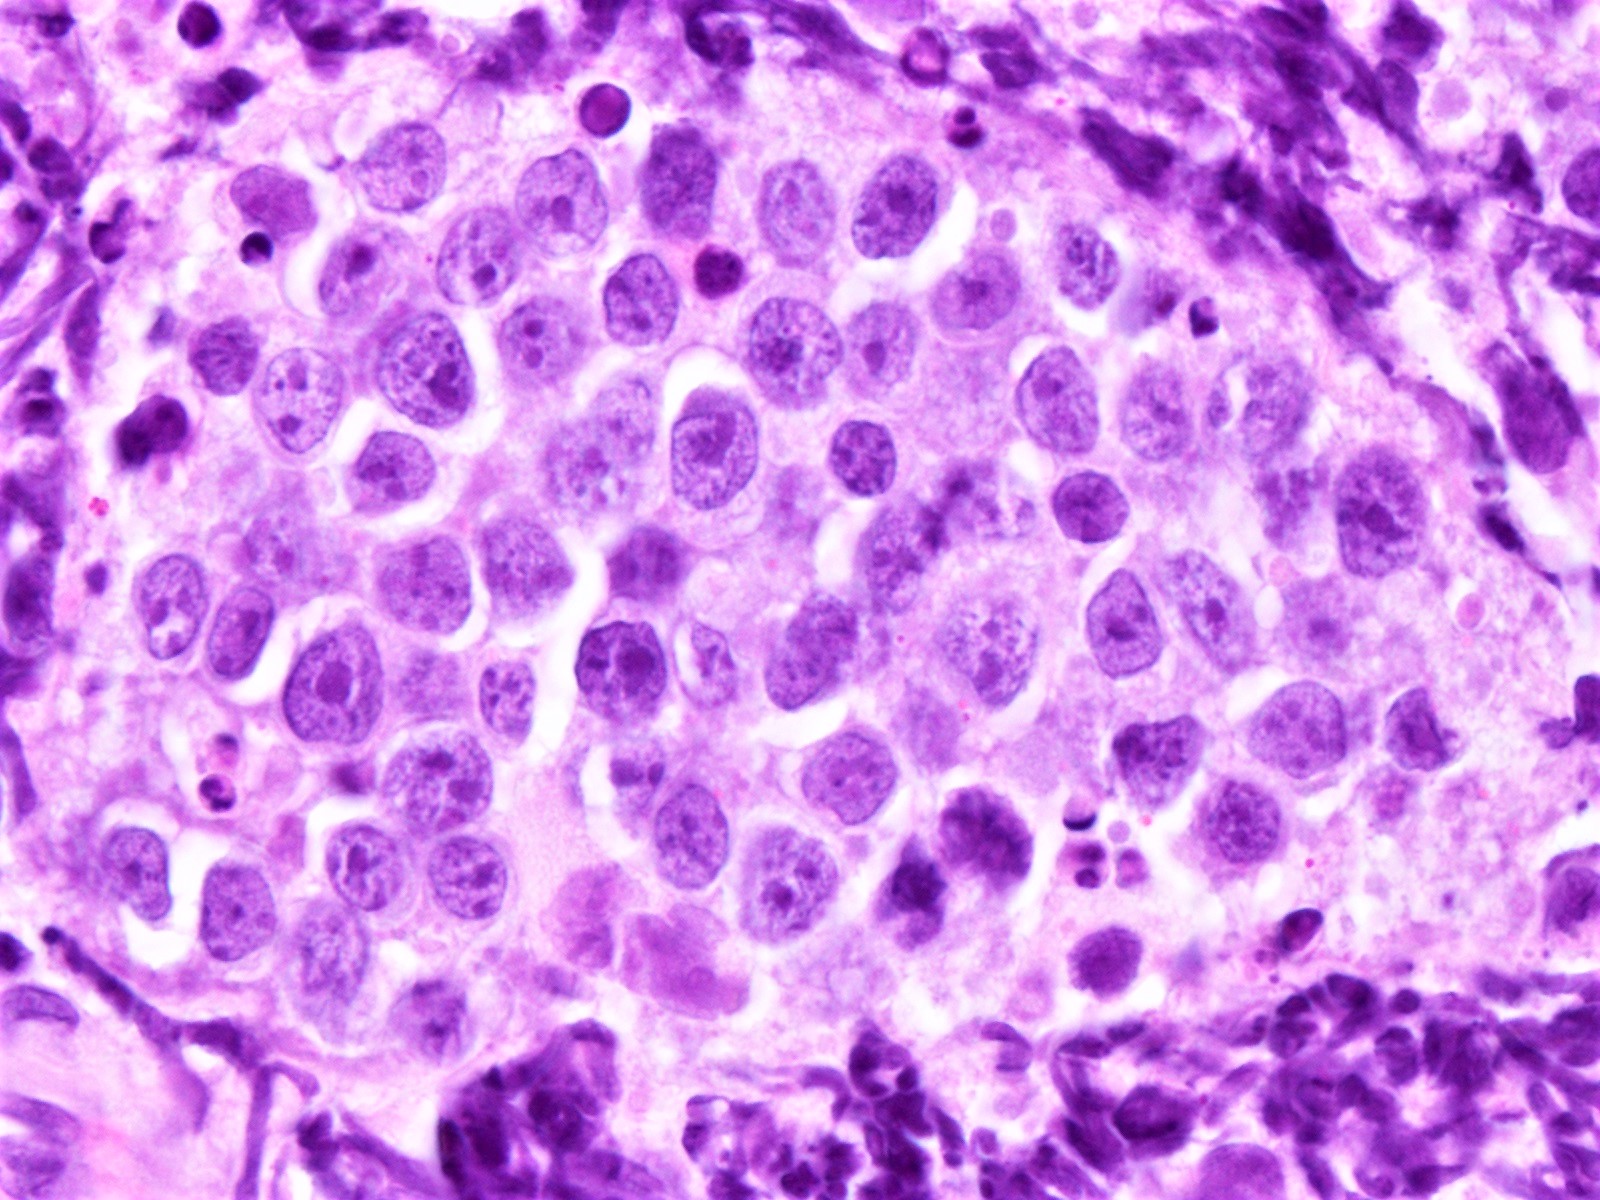

- Pleomorphic variant

- Variable size / heterogenous cell population including large cells

- Prominent nucleoli +/-

- High mitotic rate often seen

- At least 10 mitoses per 10 high power fields and often higher rates

- Resembles, in part, diffuse large B cell lymphoma

- Peripheral blood lymphocytes are intermediate sized with prominent nucleoli

- Resemble prolymphocytes to variable degree

- Multinucleation or cerebriform nuclei often seen

Microscopic (histologic) images